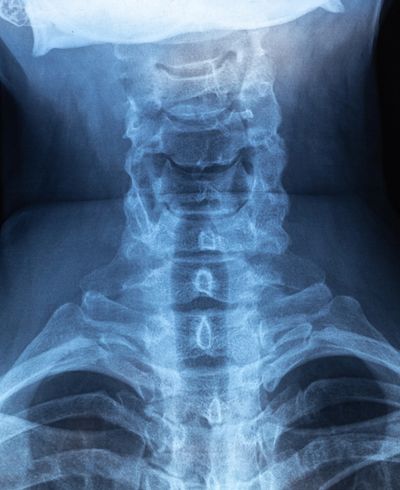

X-ray image of the cervical spine and upper thoracic region.

Maintaining Nerve & Disc Health

Many people consult a Chiropractic Physician because they think they have a pinched nerve. More common are nerves that are stretched, twisted or irritated by spinal structures. Because of the way our spine is designed, abnormal spinal function caused from physical trauma a result of work related or driving accidents, for example, emotional tension or chemical toxins can effect the delicate tissues of the spinal cord and nerve roots. More frequently, nerves are irritated (facilitative lesions). This is caused when nerve tissue is rubbed, scraped or stretched by a loss of spinal curve or irritated by malfunctioning spinal join

Technically, a disc cannot "slip." However, like the shock absorbers on your car they can leak or rupture, causing serious back pain and other issues requiring chiropractic treatment. The intervertebral disc is a pad of cartilage-type material situated between spinal bones. Each disc serves as a connector, spacer and shock absorber for the spine. A soft, jellylike center is contained by outer layers of fibrous tissue. Healthy discs allow normal turning and bending. Because of the way each disc is attached above and below the vertebrae, a disc can not "slip". However, trauma or injury to the spine can cause a disc to tear, bulge, herniate or worse, rupture. This can be quite painful, as the soft center of the disc leaks, putting pressure on the adjacent nerve roots and spinal cord. While results can not be guaranteed, many patients have avoided needless surgery or a dependency on pain pills by choosing chiropractic care for their disc related health problem